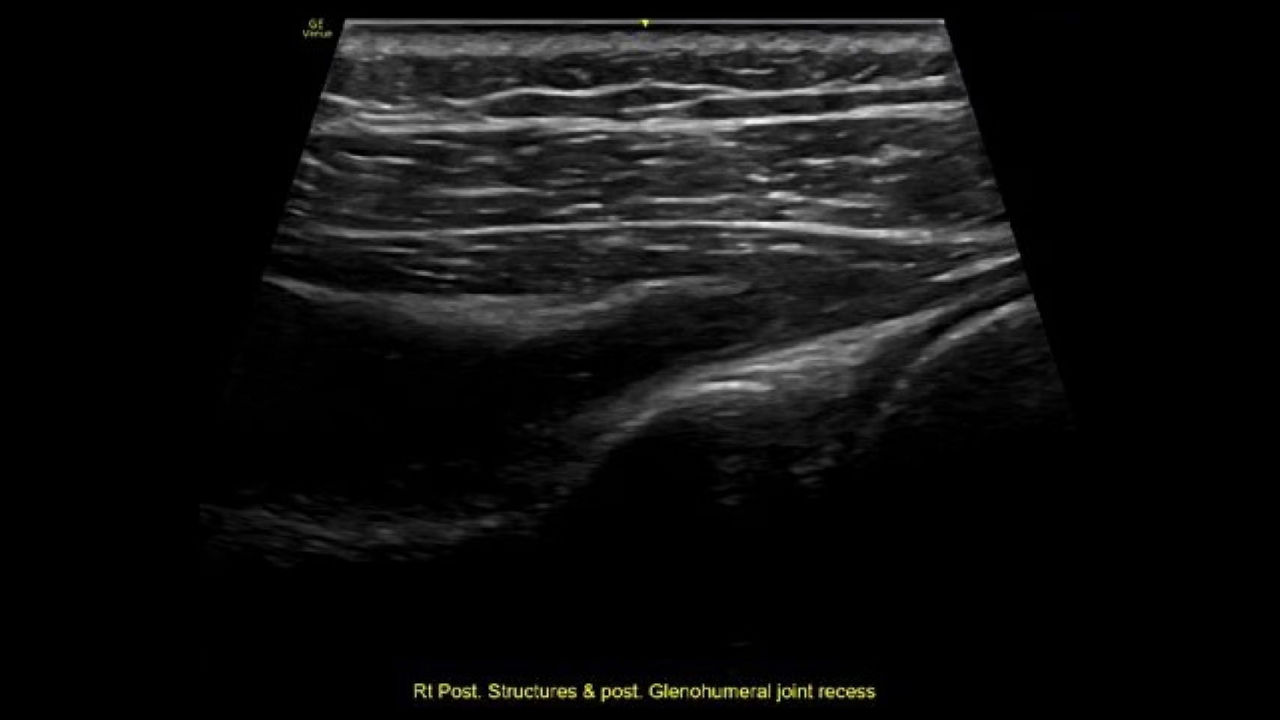

Providing musculoskeletal (MSK) practitioners with effortless and precise ultrasound, the VenueTM  family of AI-enabled point of care ultrasound systems allows you to quickly assess tendons, muscles, and joints, and manage patient progress during a course of treatment. Improving both the patient and practitioner experience, Venue family products enable fast assessments and accurate needle procedures.

Supporting MSK practitioners through a variety of features, Venue family enhances patient safety and satisfaction by removing the need for patients to reschedule additional visits.

This easy-to-use exam documentation tool assists users through exams by providing reference images and anatomy markups. Multiple anatomical areas and helpful video tutorials help clinicians to acquire the scans they need.

Focus areas include:

• Shoulder

• Knee

• Hip

• Elbow

• Wrist/Hand

• Ankle/Foot

Reference Image: Reference image provides anatomy mark-ups to assist novice users in scanning the correct anatomy